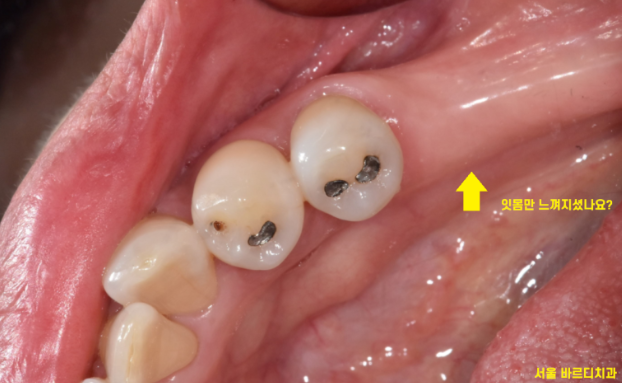

임플란트 수술 후 혀로 수술 부위를 만져보면

잇몸 밖으로 무언가가 튀어나온 것을

확인하실 수 있습니다.

이것은 임플란트는 아니고요~~

임플란트와 연결해둔 뚜껑입니다.

이렇게 뚜껑을 잇몸 밖에 두는 것을

임플란트 1회 수술법이라 합니다.

그도 그럴 것이 사진과 같은 모습이기 때문이죠~!

잇몸밖에 안보이죠~?